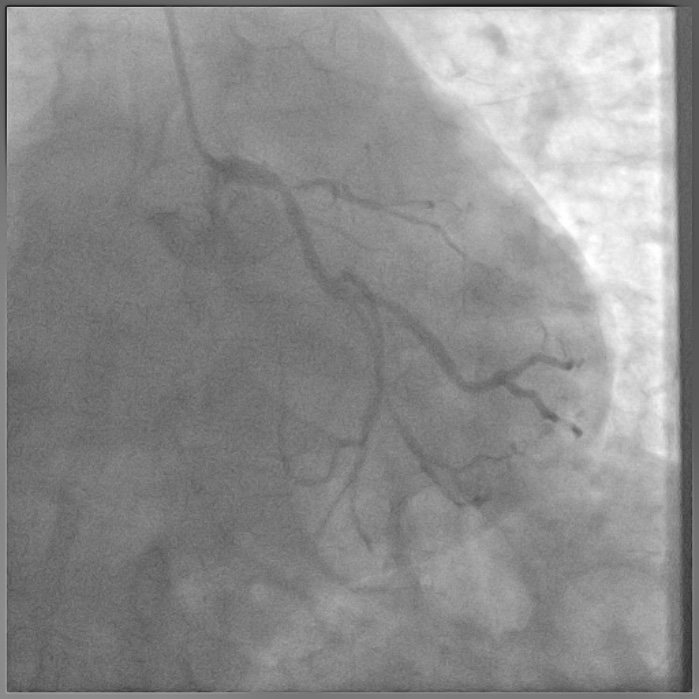

Coronary angiography done outside showed normal LM, ostial LAD cut off with retrograde filling from RCA via Grade 2 collaterals, ostial Lcx 90% stenosis (D1,D2) , large normal OM1, small and diffusely diseased OM2 and OM3, dominant RCA showing mid plaque and distal 50 % stenosis (D3).

8F JL coronary guide catheter was taken from the right femoral artery and a TIG diagnostic catheter was taken from right radial artery and bilateral angiograms were taken. A floppy guide wire was placed in Lcx and ostial Lcx lesion was predicated with a 2*12 mm non compliant balloon. An IVUS catheter was placed over Lcx wire and under IVUS guidance a Gaia 3 coronary wire (Asahi, Japan) over a micro catheter was used to probe the ambiguous osmium of LAD (T1). Using contralateral injection in RCA, the Gaia 3 wire was seen extending into the false lumen in distal LAD. A Conquest Pro 12 (Asahi, Japan) was then taken over a micro catheter using a parallel wire strategy and successfully negotiated in distal true lumen of LAD (T2). After pre dilatation of LAD, Conquest Pro wire was exchanged for a floppy guide wire over a micro-catheter. IVUS run was then taken from LAD to LM and LCx to LM for vessel sizing. In view of the discrepancy in size of LAD/LCx and LM, 2 coronary stents were placed in a V technique from LM to LAD and LM to LCx and deployed. The stents were then post dilated and final kissing balloon inflation was done and the results were optimised by IVUS. Final cine showed well expanded LM LAD/LCx stents with TIMI 3 flow (T3).